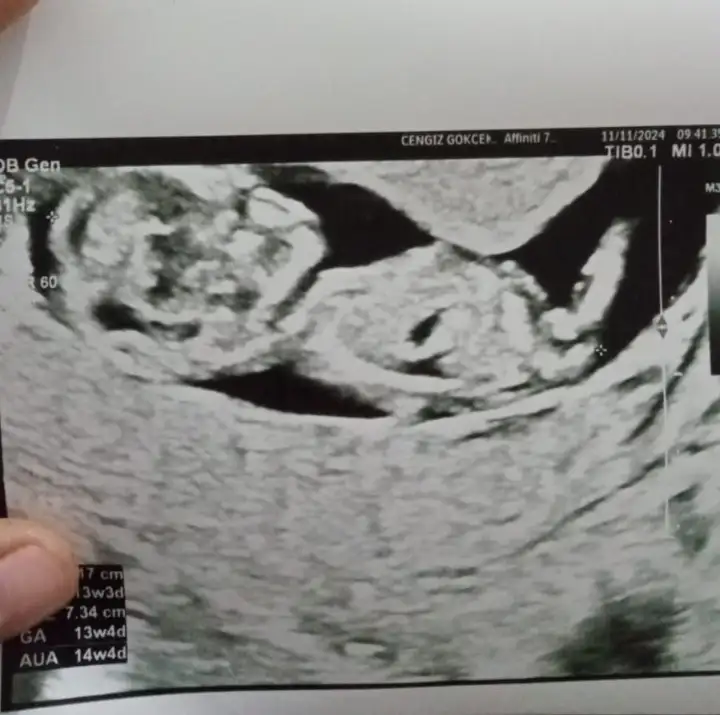

Cinsiyet tahmini

Selam bana da tahminde bulunabilir misiniz?